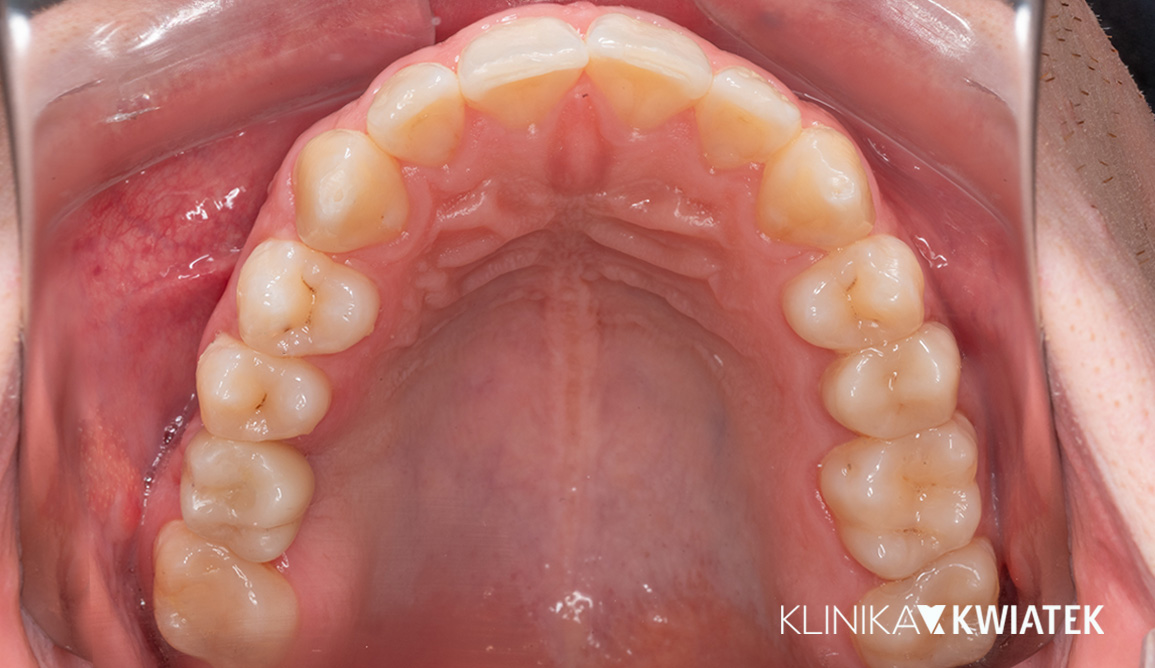

Kliniczna precyzja i estetyka – jak przywróciliśmy funkcję i piękno uśmiechu

Pacjentka zgłosiła się z wadą zgryzu, licznymi ubytkami i utraconymi zębami trzonowymi, co powodowało trudności w żuciu i estetyczne niezadowolenie. Leczenie obejmowało ekstrakcje, ortodoncję, implantację oraz kompleksową rekonstrukcję protetyczną. Po kilkunastu miesiącach terapii Pacjentka odzyskała pełną funkcję zgryzu i piękny, harmonijny uśmiech.